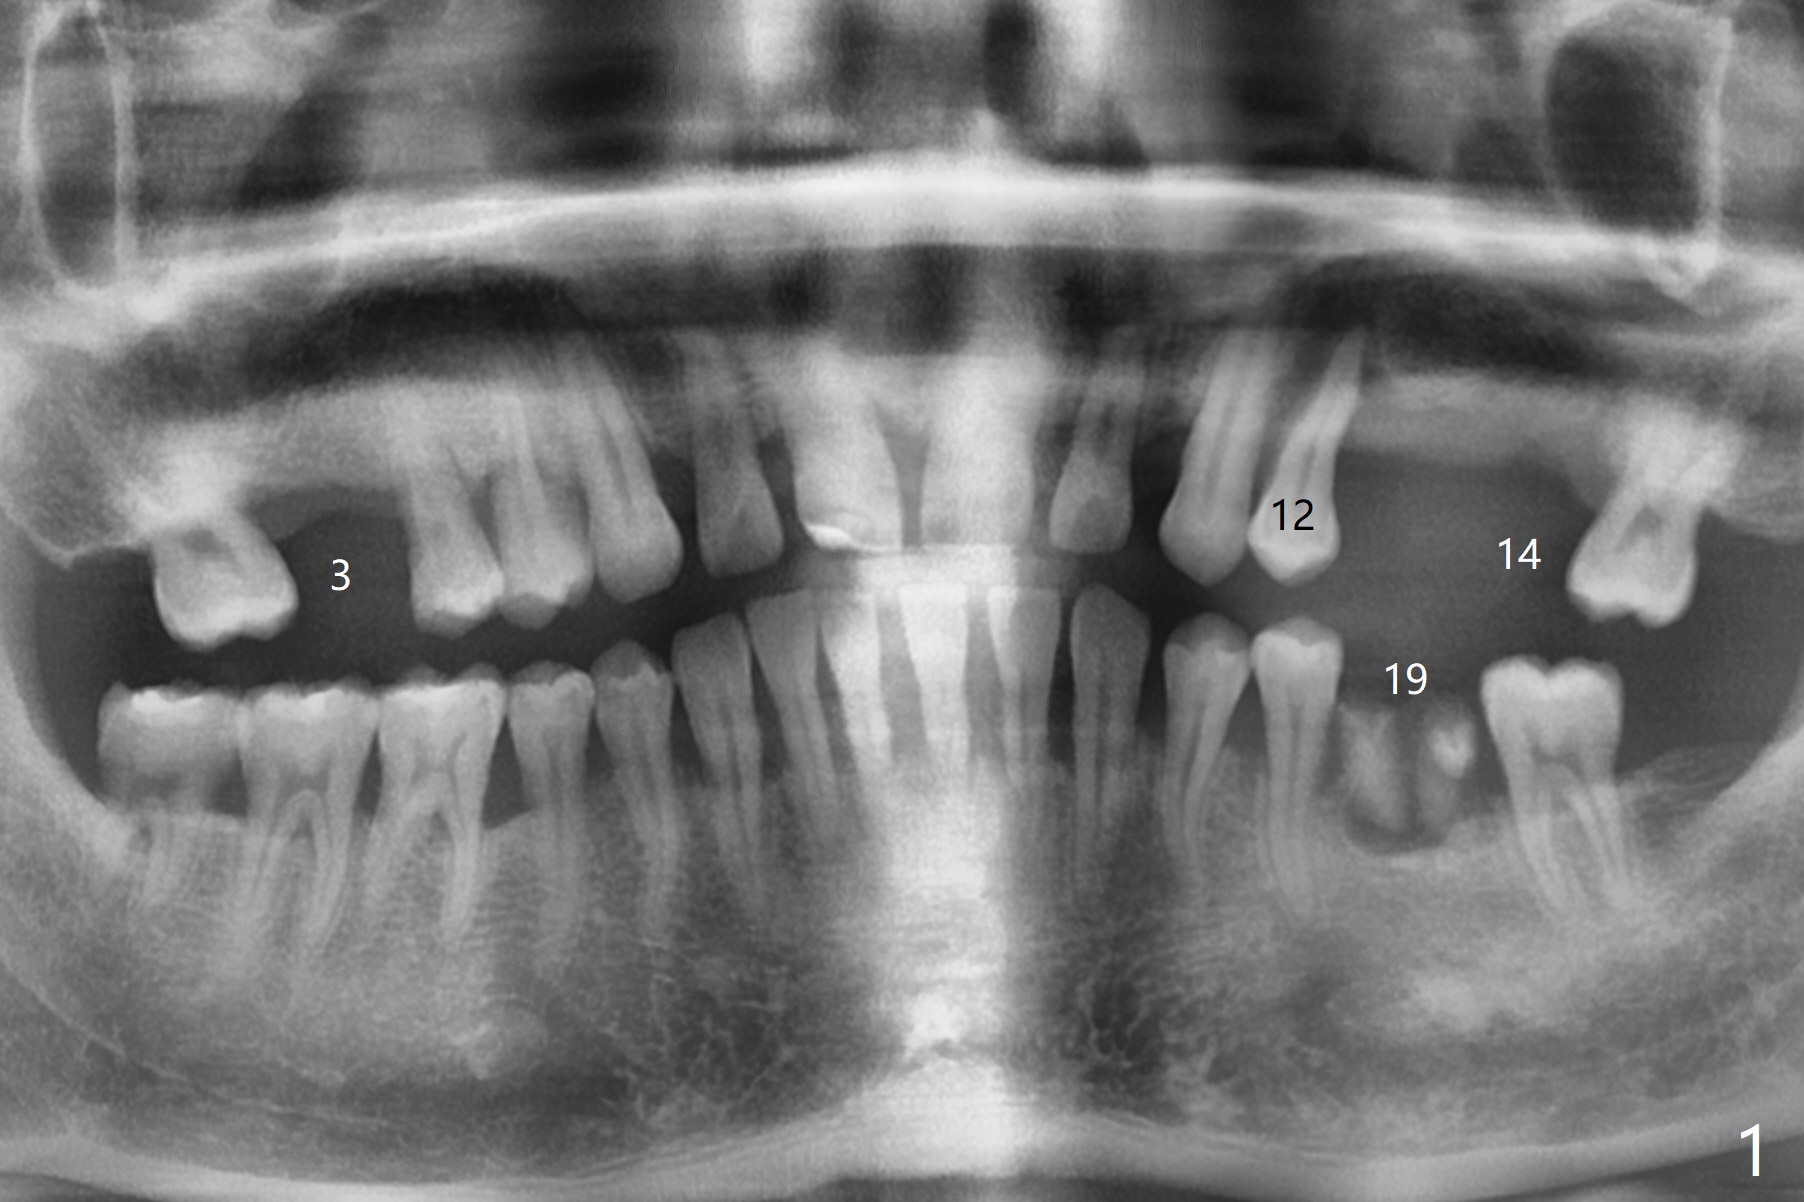

A 34-year-old man (smoker 1/2 ppd) presents to clinic for SRP and implant consultation (Fig.1). He wishes to restore UL first and the rest 2nd (Fig.2-5). Pay attention to placement level. OH will be emphasized, water pik and smoke cessation.